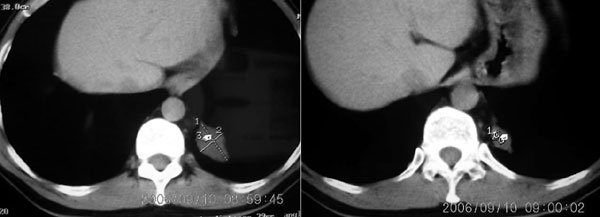

左下叶后基底段内胸主动脉旁可见一类梭形团块状影,边界较清楚,其内有小结节样高密度钙化影,肿块与胸主动脉可见条状影相连(见下图).

诊断:左下叶肺段隔离症.

支持向医生老师图示的意见,考虑隔离肺。不过,病灶内应该不是钙化,而是光标。